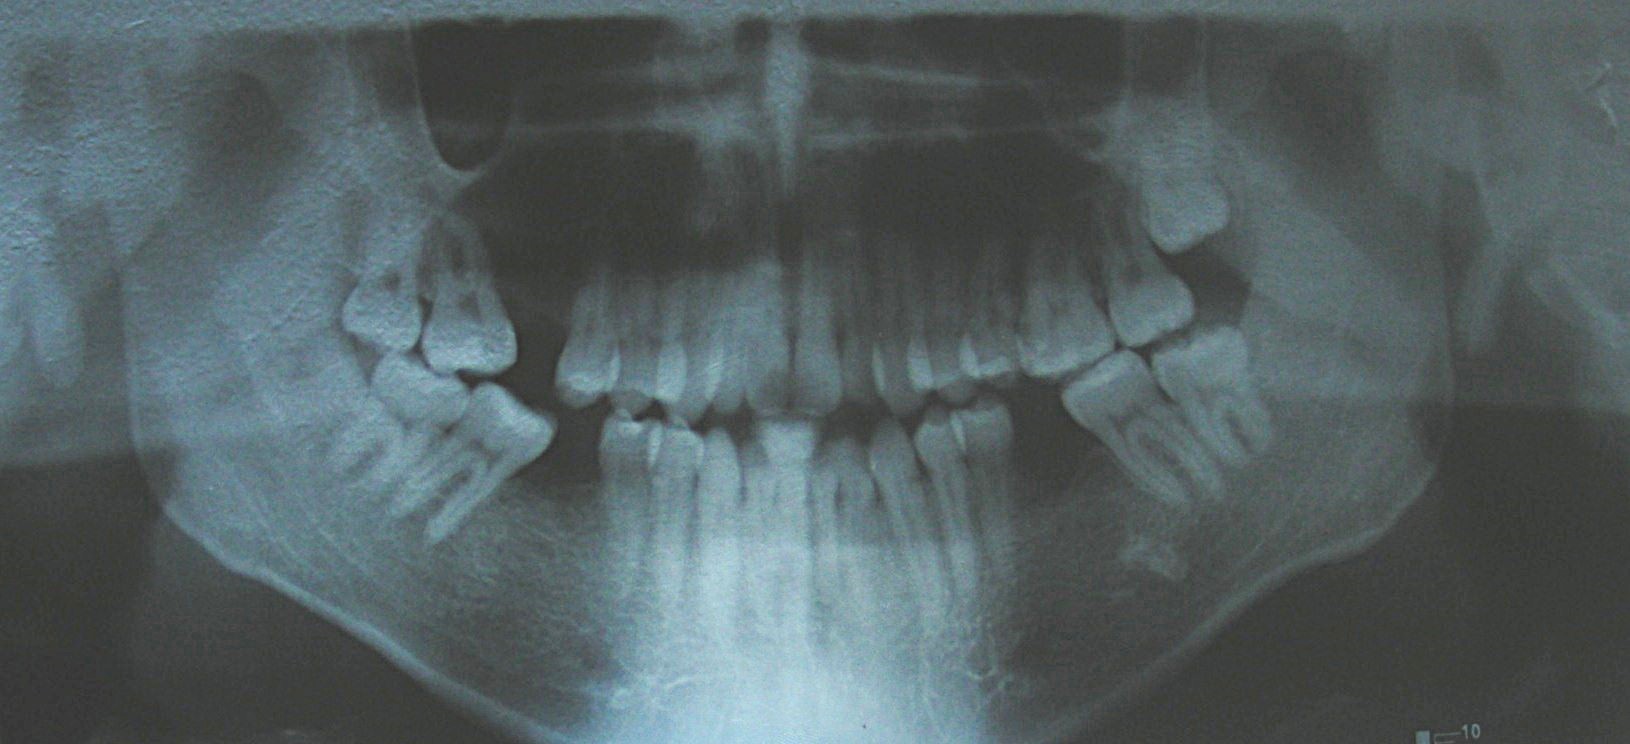

Cephalometric analysis confirmed a vertical skeletal discrepancy, consistent with a skeletal-based anterior open bite. The initial treatment plan involved a combined orthodontic-surgical approach, including bimaxillary surgery: Le Fort I impaction osteotomy with preliminary surgically assisted maxillary expansion and bilateral sagittal split osteotomy (BSSO), with possible genioplasty.

Absent #16, #36 and #46 , No Angle molar relationship . Projection of canines axes in class II relationship . Anterior open bite: Over Bite – 8 mm). Bilateral posterior crossbite: Involvement of upper posterior sectors with inverted buccal-lingual relationship. Moderate Crowding at the level of the upper and lower incisors. Acceptable Oral Hygiene with no periodontal issues

Cephalometric diagnosis

| Parameter | Patient (22yo) | Normal | Interpretation |

|---|---|---|---|

| Facial Axis | 79° | 90° ± 3° | Decreased – indicative of vertical growth pattern– dolichofacial |

| Facial Depth | 89° | 90°± 3° | Slightly reduced (N) – dolichofacial tendency |

| Mandibular Plane Angle | 31° | 22° ± 4° | Increased – dolichofacial tendency |

| Lower Facial Height | 56° | 47 ± 4° |

Increased – long lower third– dolichofacial |

|

Convexity (A–N–Pog) |

+1 mm | ±2 mm | Normal |

| Upper Incisor to A-Pog | 8 mm | 2–4 mm | Proclined upper incisors |

Inclination lower Incisor |

19° | 22° | Retroclined lower incisors |

| Interincisal angle | 129° | 130° ± 6° | Decreased – flaring of incisors |

| Maxillary–Mandibular plane angle (MM angle) | 31° | 22° ± 4° | Increased – open bite tendency |

| Mandibular arc | 30° | 31 °± 2 | Slightly reduced– dolichofacial tendency |

| Cranial deflection | 34° | 27° ± 4° | Mildly increased |